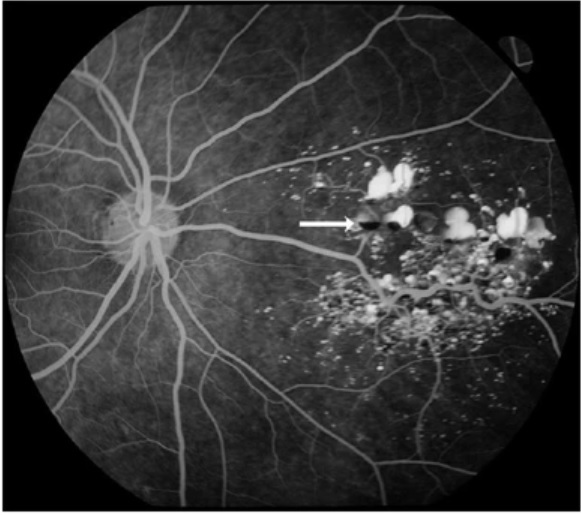

Qual é o padrão de herança do Hemangioma Cavernoso da Retina?

- Esporádico (mais comum - restritos à retina)

- Autossômica Dominante (associados à hemangiomas cutâneos e intracranianos)

Quais são os achados típicos do Hemangioma Cavernoso da Retina?

Quais são os principais achados do Hemangioma Cavernoso de Retina no exame de Angiografia com Fluoresceína?